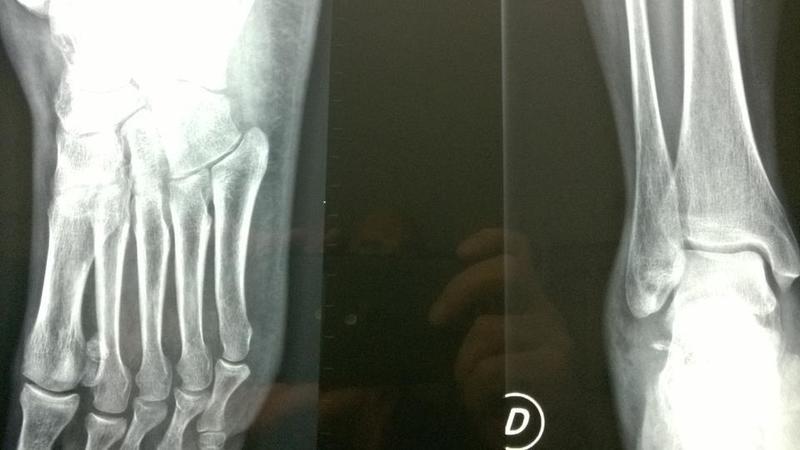

Frattura del malleolo peroneale composta o scomposta ...

Frattura del malleolo peroneale composta o scomposta ... from www.fisioterapiarubiera.com

L'osso che è stato rotto è chiamato metatarso. La frattura del metatarso 5 generalmente ha un trattamento conservativo, cioè immobilizzazione e in alcuni casi, la frattura del quinto metatarso del piede richiede una terapia fisica, tuttavia ci sono. Tutore per frattura v metatarso.